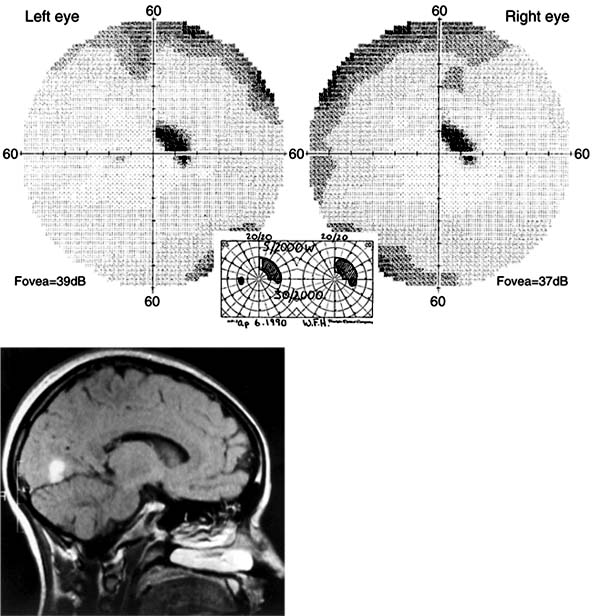

Figure 14-4: Occipital lobe abscess. Top: Automated perimetry and tangent screen examination showing homonymous, congruous, paracentral scotoma in right upper visual fields. Bottom: Parasagittal MRI showing lesion involving left inferior calcarine cortex. (Reproduced, with permission, from Horton JC, Hoyt WF: The representation of the visual field in human striate cortex. A revision of the classic Holmes map. Arch Ophthalmol 1991;109:816.)

Figure 14-5

Figure 14-5: Bilateral occipital infarcts with bilateral macular sparing. Top: Tangent screen and superimposed Goldmann visual fields of both eyes showing bilateral homonymous hemianopia with macular sparing, greater in the right hemifield. Bottom: Axial MRI showing sparing of occipital poles. (Reproduced, with permission, from Horton JC, Hoyt WF: The representation of the visual field in human striate cortex. A revision of the classic Holmes map. Arch Ophthalmol 1991;109:816.)